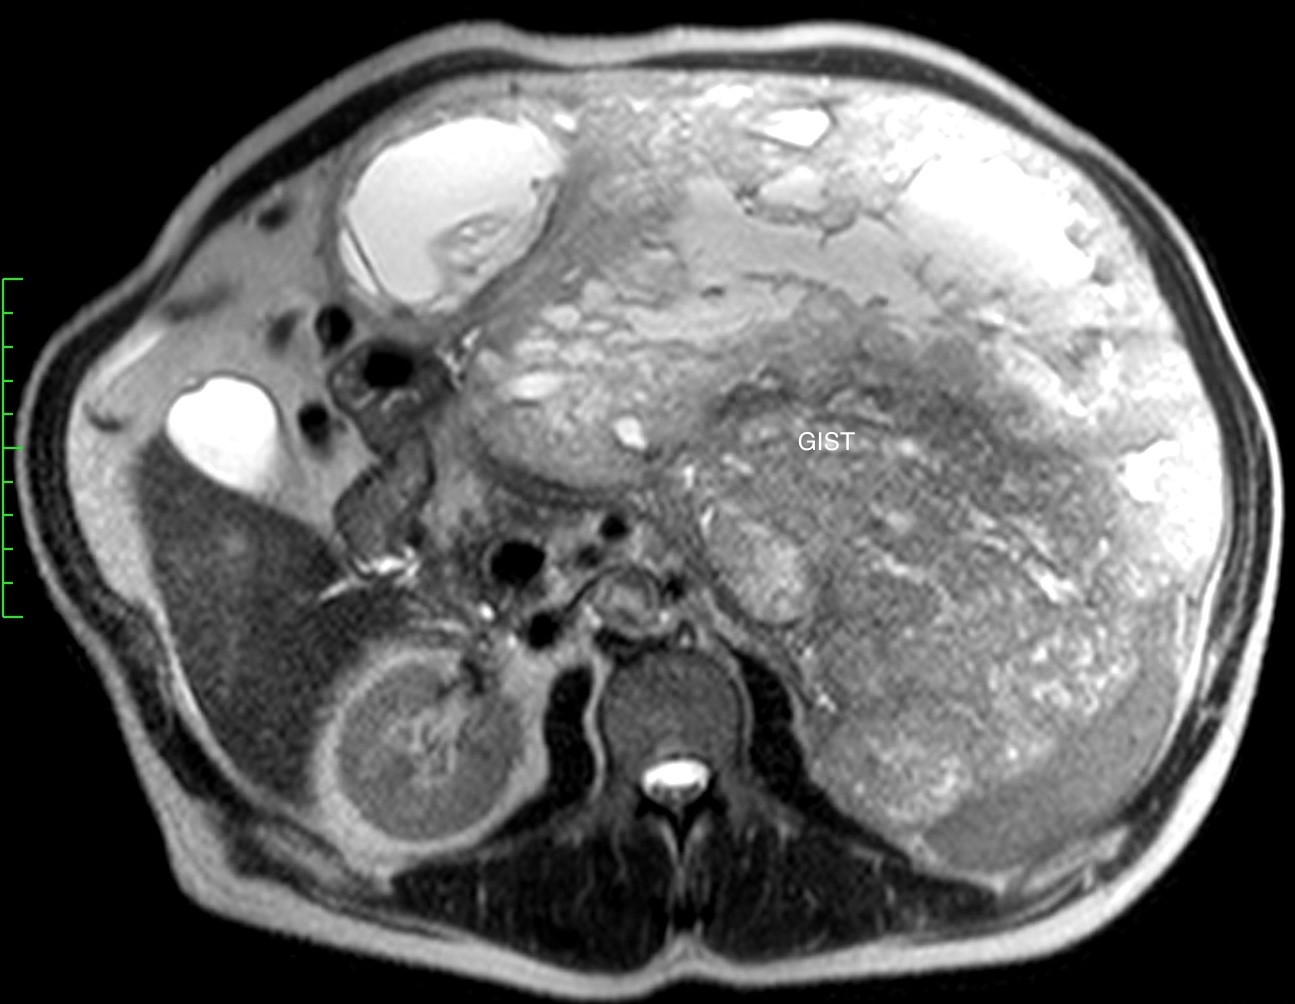

Гастроинтестинальная стромальная опухоль гигантских размеров, исходящая из большой кривизны желудка